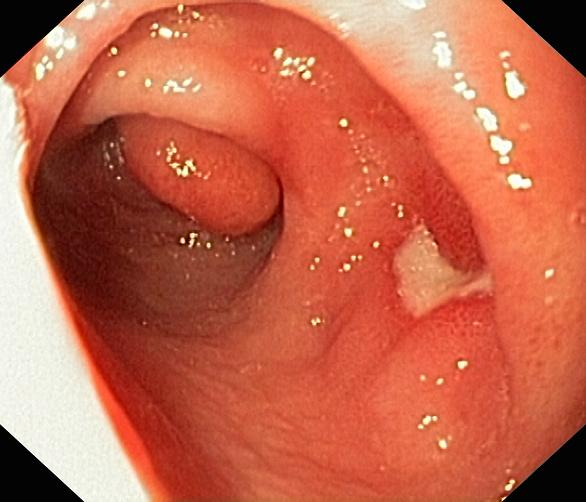

Wrzód trawienny